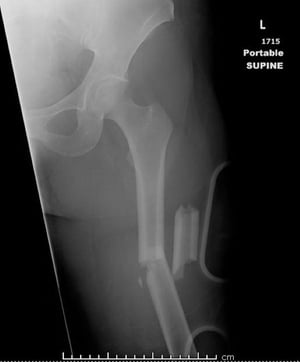

Перелом середньої частини стегнової кістки (1)

На цьому зображенні показано уламковий перелом діафіза стегнової кістки з кутовою деформацією та укороченням.

Знімок люб'язно надано лікарем Даніелем Кампаньє [Danielle Campagne], MD.